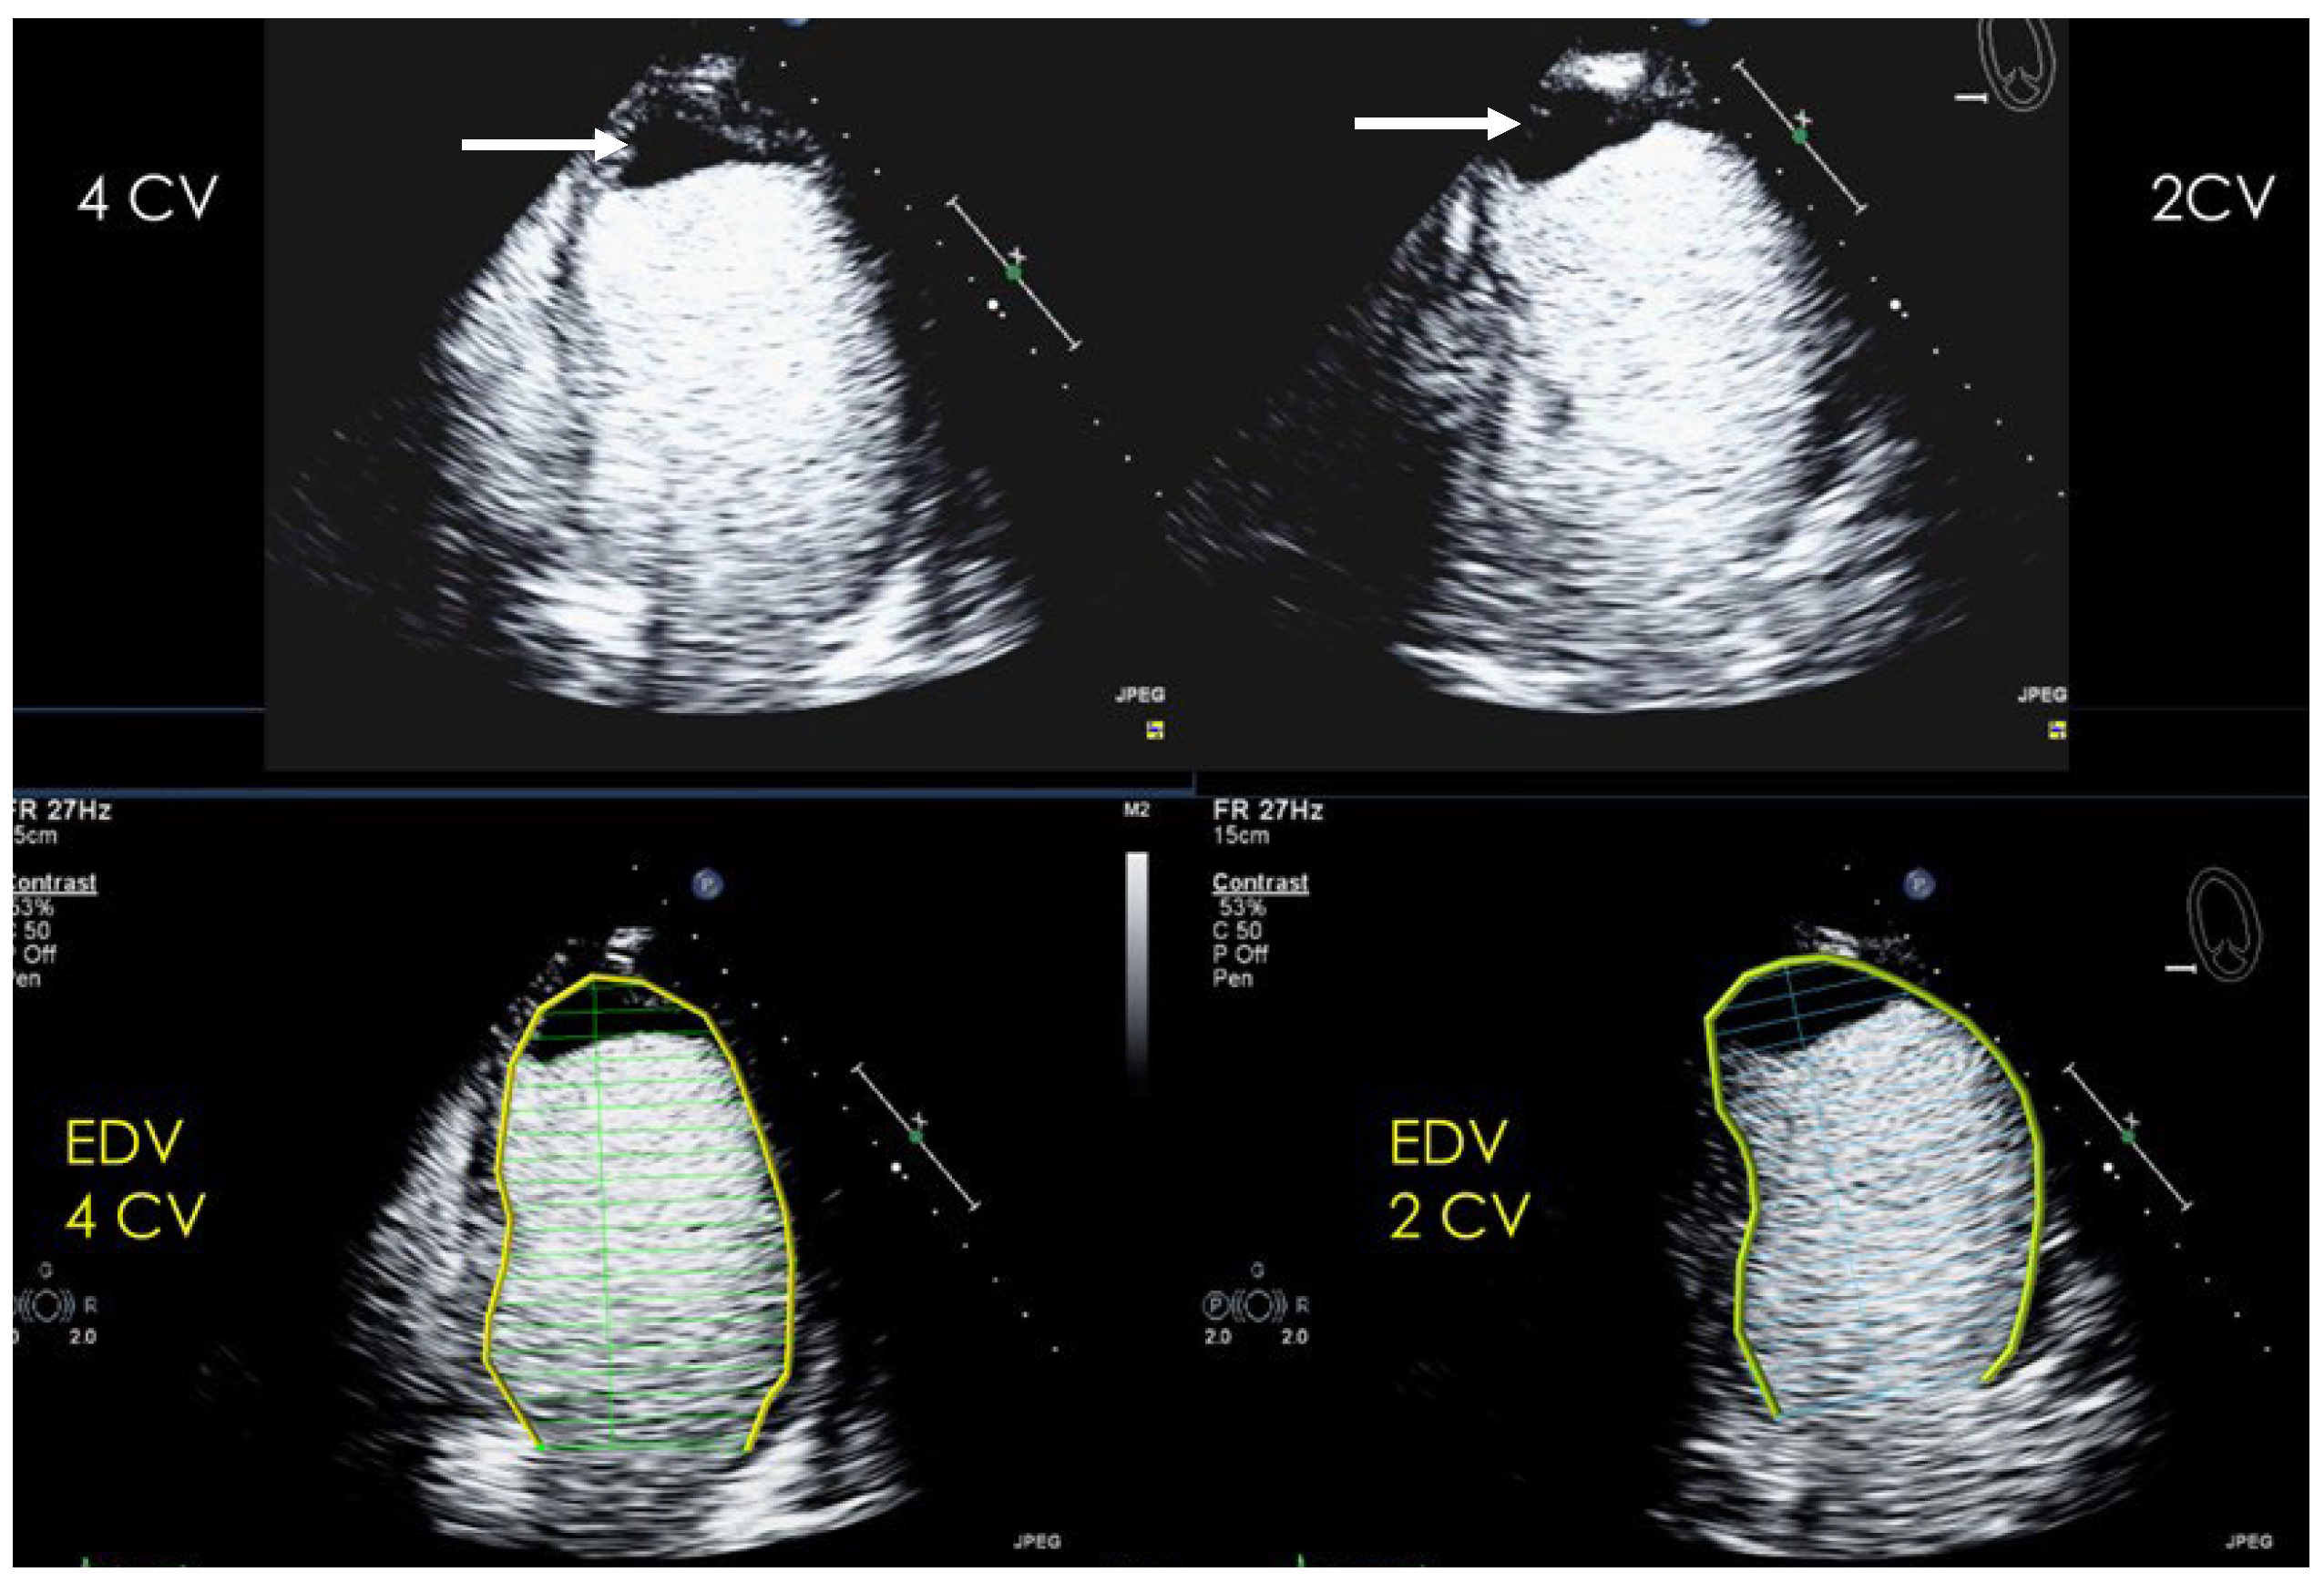

| Imaging method | Low-MI-contrast-specific imaging and intermediate-MI-contrast-specific imaging |

| Imaging planes | standard apical views additional zoomed views sweeps through the region of the suspected thrombus |

| Sector depth/width | Entire LV + 1/3 LA to assess global/regional LV function, zoomed views of the region with the suspected thrombus |

| Focus | At the depth of the suspected thrombus |

| Gain | Adjust to avoid obscuring the thrombus by intensive opacification of the cavity |

| Contrast application | bolus injections |

| Typical findings | 1. echofree mass 2. present in two different imaging planes 3. lump or laminar shape different from trabeculations’ documented size (two orthogonal diameters in at least one of the views), location, type (laminar vs. lump, single vs. multiple), surface (smooth vs. irregular) and mobility |